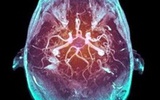

大脑扫描技术能反映人类疼痛状况

英国的神经科学家采用的是大脑扫描技术,能看到疼痛时大脑的反应,并能精确得知疼痛点和疼痛的强度。这门技术或许可以帮助那些认为同伴夸大疼痛症状的人,能科学地验证同伴疼痛的轻重和真伪。

大脑扫描

疼痛地图

脑部信号

痛觉